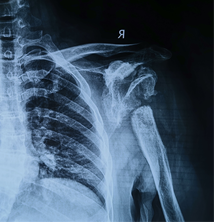

术前X线,肱骨头,肩关节盂缺损严重

患者女,44岁,患者于入院前1月余出现右肩部间断疼痛不适,伴活动受限,偶有上肢皮肤麻木,局部皮肤完整,无擦伤及活动性出血,无肿胀,青紫及瘀斑,就诊于当地医院行肩关节影像检查示:右侧肱骨头坏死改变,右侧肩关节结构紊乱,正常结构消失,肱骨头缺血坏死样改变。

当地医院建议转上级医院治疗,患者以“夏科氏肩关节病”收住科室。患者存在脊髓空洞症,右肩受累关节端硬化更明显,伴骨质增生、破坏、骨膜反应、关节脱位、关节面破坏、塌陷,关节脱位,关节周围软组织肿胀,软组织内不规则钙化斑或碎骨片。关节周围肩袖松弛缺失。